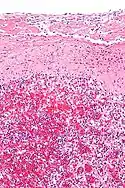

En el uso médico histopatológico, una sustancia hialina aparece vidriosa y rosada después de teñirse con hematoxilina y eosina, por lo general, es un material acelular y proteináceo. Un ejemplo es el cartílago hialino, un cartílago articular transparente y brillante.[3]

La hialina arterial se observa en el envejecimiento, la presión arterial alta, la diabetes mellitus y en asociación con algunos medicamentos (por ejemplo, inhibidores de la calcineurina). Es de color rosa brillante con tinción PAS.